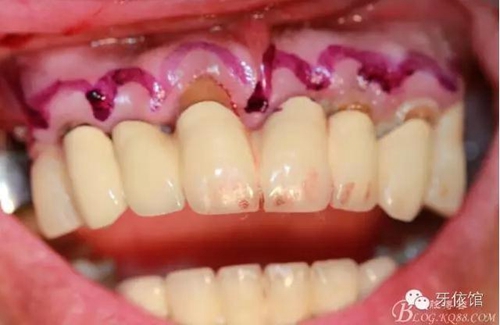

術(shù)中口內(nèi)照

降低骨高度,左右1,2骨寬度嚴(yán)重不足,決定將前牙2——2區(qū)間植體植在切牙孔內(nèi)

左右3牙位分別植入一顆

這個角度看1,2牙位骨寬度是不是很???僅2mm